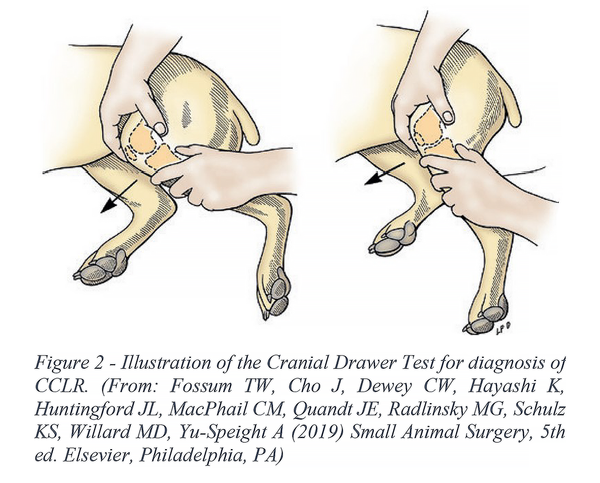

Đứt dây chằng chéo trước (CCL) là nguyên nhân phổ biến nhất khiến chó khập khiễng chân sau. Tình trạng này thường xảy ra khi chó xoay người hoặc nhảy mạnh. Triệu chứng điển hình gồm: chó không đặt chân xuống đất, tư thế ngồi duỗi chân bị thương ra ngoài, sưng khớp gối và teo cơ nếu kéo dài. Dấu hiệu ‘ngăn kéo trước’ (Drawer Sign) là tiêu chuẩn vàng trong chẩn đoán, cần bác sĩ thú y kiểm tra.